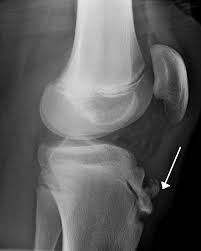

Diagnosis is made clinically with an enlarged tibial tubercle and supplemented with radiographs of the knee that reveal irregularity and fragmentation of the tibial tubercle. Osgood-Schlatter disease is an overuse injury of the knee common in growing adolescents. Osgood-Schlatter is a common disease with most cases resolving spontaneously with skeletal maturity.

Osgood Schlatter Disease Collection Of Plain X Rays